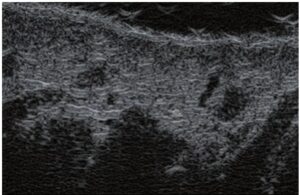

La ecografía Doppler permite obtener imágenes de grandes vasos y perforantes que suelen estar situados en las capas más profundas del tejido subcutáneo (fig. 1). Desgraciadamente, la ecografía convencional no es capaz de obtener imágenes de vasos más pequeños. Para visualizar los vasos más pequeños situados cerca de la superficie de la epidermis y en la capa superior del tejido subcutáneo, se utiliza el HFU (fig. 1). Gracias al uso de transductores con frecuencias superiores a 20 MHz, se obtiene una imagen ecográfica de alta resolución en la que podemos diferenciar estructuras menores de 0,1 mm. Sin embargo, cuanto mayor es la resolución, menor es la penetración del haz de ultrasonidos en las capas de la piel. Por lo tanto, dependiendo del transductor y del aparato, es posible penetrar en la piel hasta una profundidad de 20-30 mm como máximo. Tal penetración, junto con la alta resolución de la imagen, permite la evaluación incluso de vasos sanguíneos muy pequeños (fig. 2). Durante el examen con el uso de transductores de alta frecuencia, se puede evaluar con precisión el curso y la ubicación de los pequeños vasos en la piel. Esto es particularmente relevante para la selección del método de cierre del vaso y la planificación del procedimiento ya que, en la práctica, la superficie de la piel muestra muy a menudo únicamente un pequeño número de vasos o un ligero fragmento de un vaso; solo tras el examen por ecografía podemos determinar su número y curso reales. Para un cierre eficaz del vaso, es necesario hacerlo en toda su longitud. No debe limitarse al fragmento visto «a simple vista» en la superficie de la piel, ya que el cierre del fragmento causará su rápida recanalización(7). Con frecuencia, el vaso visible en la superficie de la piel cambia su curso, se vuelve más tortuoso y se desplaza a las capas más profundas de la piel(8). Por lo tanto, el curso de la vena y las perforantes deben conocerse y determinarse bien antes del procedimiento. El HFU también permite obtener imágenes de las perforantes entre pequeños vasos. Además, aparte de la evaluación del curso y la anatomía, la imagen ecográfica, gracias al software de ultrasonidos, también permite determinar los parámetros básicos como el diámetro del vaso, el grosor de su pared, la profundidad en la piel así como la presencia o ausencia de perfusión en el interior del vaso(6) (fig. 3). Gracias al transductor electrónico multielemento con la frecuencia de 40 MHz introducido en el mercado por Ultrasonix, también es posible visualizar la perfusión en los vasos en el modo Doppler color (fig. 4).

La escleroterapia es una técnica de cierre de vasos como resultado de inyectarles un esclerosante químico. En la actualidad, se aplica habitualmente y se caracteriza, sobre todo, por sus bajos costes y por el hecho de que es relativamente fácil de realizar. La escleroterapia está indicada principalmente para el cierre de venas reticulares mayores de 3 mm, pero también puede aplicarse si los vasos son más pequeños(10). En el caso de vasos menores de 3 mm, es más difícil introducir una aguja en su luz, lo que aumenta el riesgo de complicaciones(7). En tal situación, el HFU resulta de gran ayuda. Permite visualizar con precisión el curso del vaso y, posteriormente, facilita la realización del procedimiento con guía ecográfica (fig. 6). Así, gracias a la ultrasonografía, se ha eliminado el riesgo de administrar el esclerosante fuera de la luz del vaso, lo que conlleva necrosis. La imagen por ultrasonidos de alta frecuencia también puede utilizarse para monitorizar la eficacia del procedimiento.